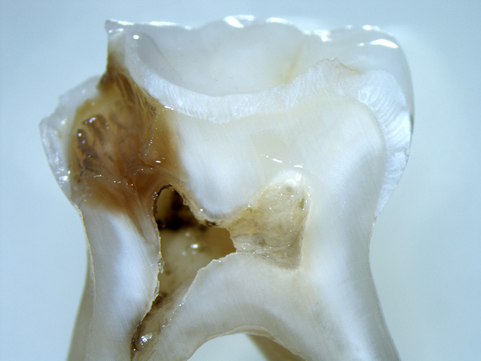

Öncelikle hastanın işlem yapılacak diş bölgesine lokal anestezi uygulanır ve kanal tedavisi yapılacak olan diş uyuşturulur. Bu sayede tedavi esnasında hasta herhangi bir ağrı veya acı hissetmez. Daha sonra dişte mevcut olan tüm çürük doku temizlenir ve çürük dişin sinirlerini de etkilediği için o bölgeye kadarda dişte bir boşluk oluşturulur

Damar ve sinir bulunan dişin merkezindeki bu odaya ve kök kanallarının içine bu noktadan ulaşılır ve çeşitli özel aletler sayesinde köklerin içleri temizlenip dezenfekte edilir. Tamamen temizlendiğinden ve bakterilerden arındığına inandığımız kök kanallarının içi özel ve doku dostu bir dolgu maddesiyle doldurulur.

Eğer kök kanalları tamamen tek seferde temizlenmediyse ve dişte aktif bir abse iltihap mevcut ise kök kanallarının içi ortamı dezenfekte eden bir malzemeyle doldurulur ve üzeri geçici olarak kapatılır. Kök ucunda iyileşme gerçekleşene kadar bu işlem seans seans tekrarlanmaktadır. Dişin durumuna bağlı olarak kanal tedavisi tek yada çok seans sürebilmektedir. Kök kanallarının dolgusunun yapılmasından sonra dişin final restorasyonu yapılmaktadır.